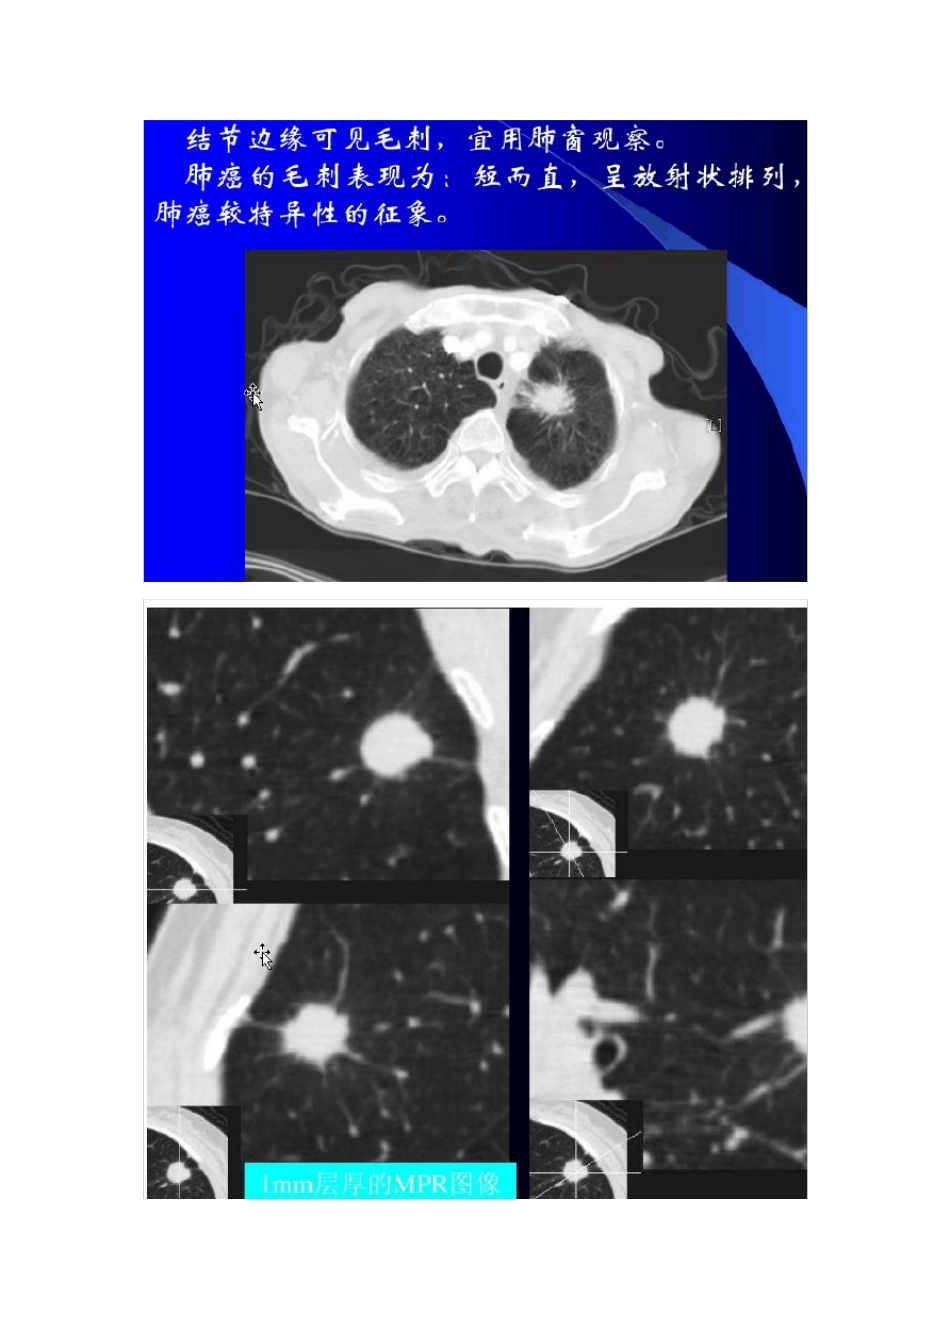

周围型肺癌的CT 诊断与鉴别诊断 周围型小肺癌诊断较困难,症状较少,常与其他病变混淆,易误诊,现将近年来对周围型肺癌的CT 的诊断与鉴别诊断的内容综述如下,以提高诊断水平。| 周围型肺癌系指发生于肺段以下支气管直到细小支气管的肺癌,临床症状出现较晚,以腺癌、鳞癌多见。目前胸部 CT 检查仍是发现肺癌最重要的检查方法,CT 在发现肺内结节方面显著优于平片及普通体层摄影,尤其是平片易被心影后方、后肋膈角、奇静脉食管隐窝、肺尖、胸膜下与肋骨重叠等遮盖的部位[1]。因此本文对周围型肺癌的CT 诊断与鉴别诊断综述如下,旨在探讨CT 对诊断周围型肺癌的临床价值及意义。| 1 周围型肺癌的CT 表现|, 1.1 病灶的形态和境界|, (1)分叶征:瘤较大常呈分叶状肿块,分叶的深浅程度对鉴别良、恶性有一定帮助。肺癌、结核球、炎性结节和其他良性病变均可出现。肺癌时有血管进入分叶间,形成脐凹征或称为支气管血管切迹。 (2)毛刺征:是周围型肺癌的又一恶性征象,分为粗毛刺和细毛刺两种。两种毛刺长度、数目及粗细均不同,其中粗毛刺较长,数目较少,粗细不均,可有扭曲。而细毛刺短而直,数目较多,CT 表现为呈放射状围绕肿瘤排列。 (3)棘状突起:表现为自肿瘤边缘向肺野内伸出的尖角状软组织密度阴影。数目不一,密集排列者可呈锯齿状外观,变换成肺窗可见由棘状突起向外延伸为毛刺,可见此棘状突起即为毛刺的根基部,系肺泡间隔与肿瘤表面重叠构成,薄层面扫描有助显示,其代表肿瘤 浸润性生长。 1.2 癌灶内部CT 表现 1.2.1 密度肿瘤多呈软组织密度,其内可有不规则低密度区;增强检查,低密度区更为明确,其代表瘤内坏死组织。癌结节分为实性密度、磨玻璃密度和混合密度。关于磨玻璃密度,需要注意:当磨玻璃密度结节持续存在数月,则提示早期肺癌。当结节大于 1cm或 者 混 有实性密度结节, 则提 示 恶 性度高 。 1 .2 .2 空洞征2 %~4 %肿瘤发生空洞,内有气体,洞壁厚而不规则。 1.2.3 空泡征和细支气管征直径小于2cm 肿瘤内可见细小充气的细支气管影,病理上为瘤组织所包绕的正常或轻度扩张的细支气管。需要与结核相鉴别,结核空洞有时也类似空泡征。 1.2.4 结节的钙化分为良性钙化和恶性钙化两种。良性钙化的特点:钙化占结节的10%以上。形态:层状、中心巢状、爆米花样或者弥散状。需要与成骨肉瘤或者软骨肉瘤的肺转移相区别。肺癌钙化的特点:形态:斑点状、斑片样、云絮状:特点是密度较低,是在肿瘤坏死基础上发生的钙化,比如大肿瘤发生...